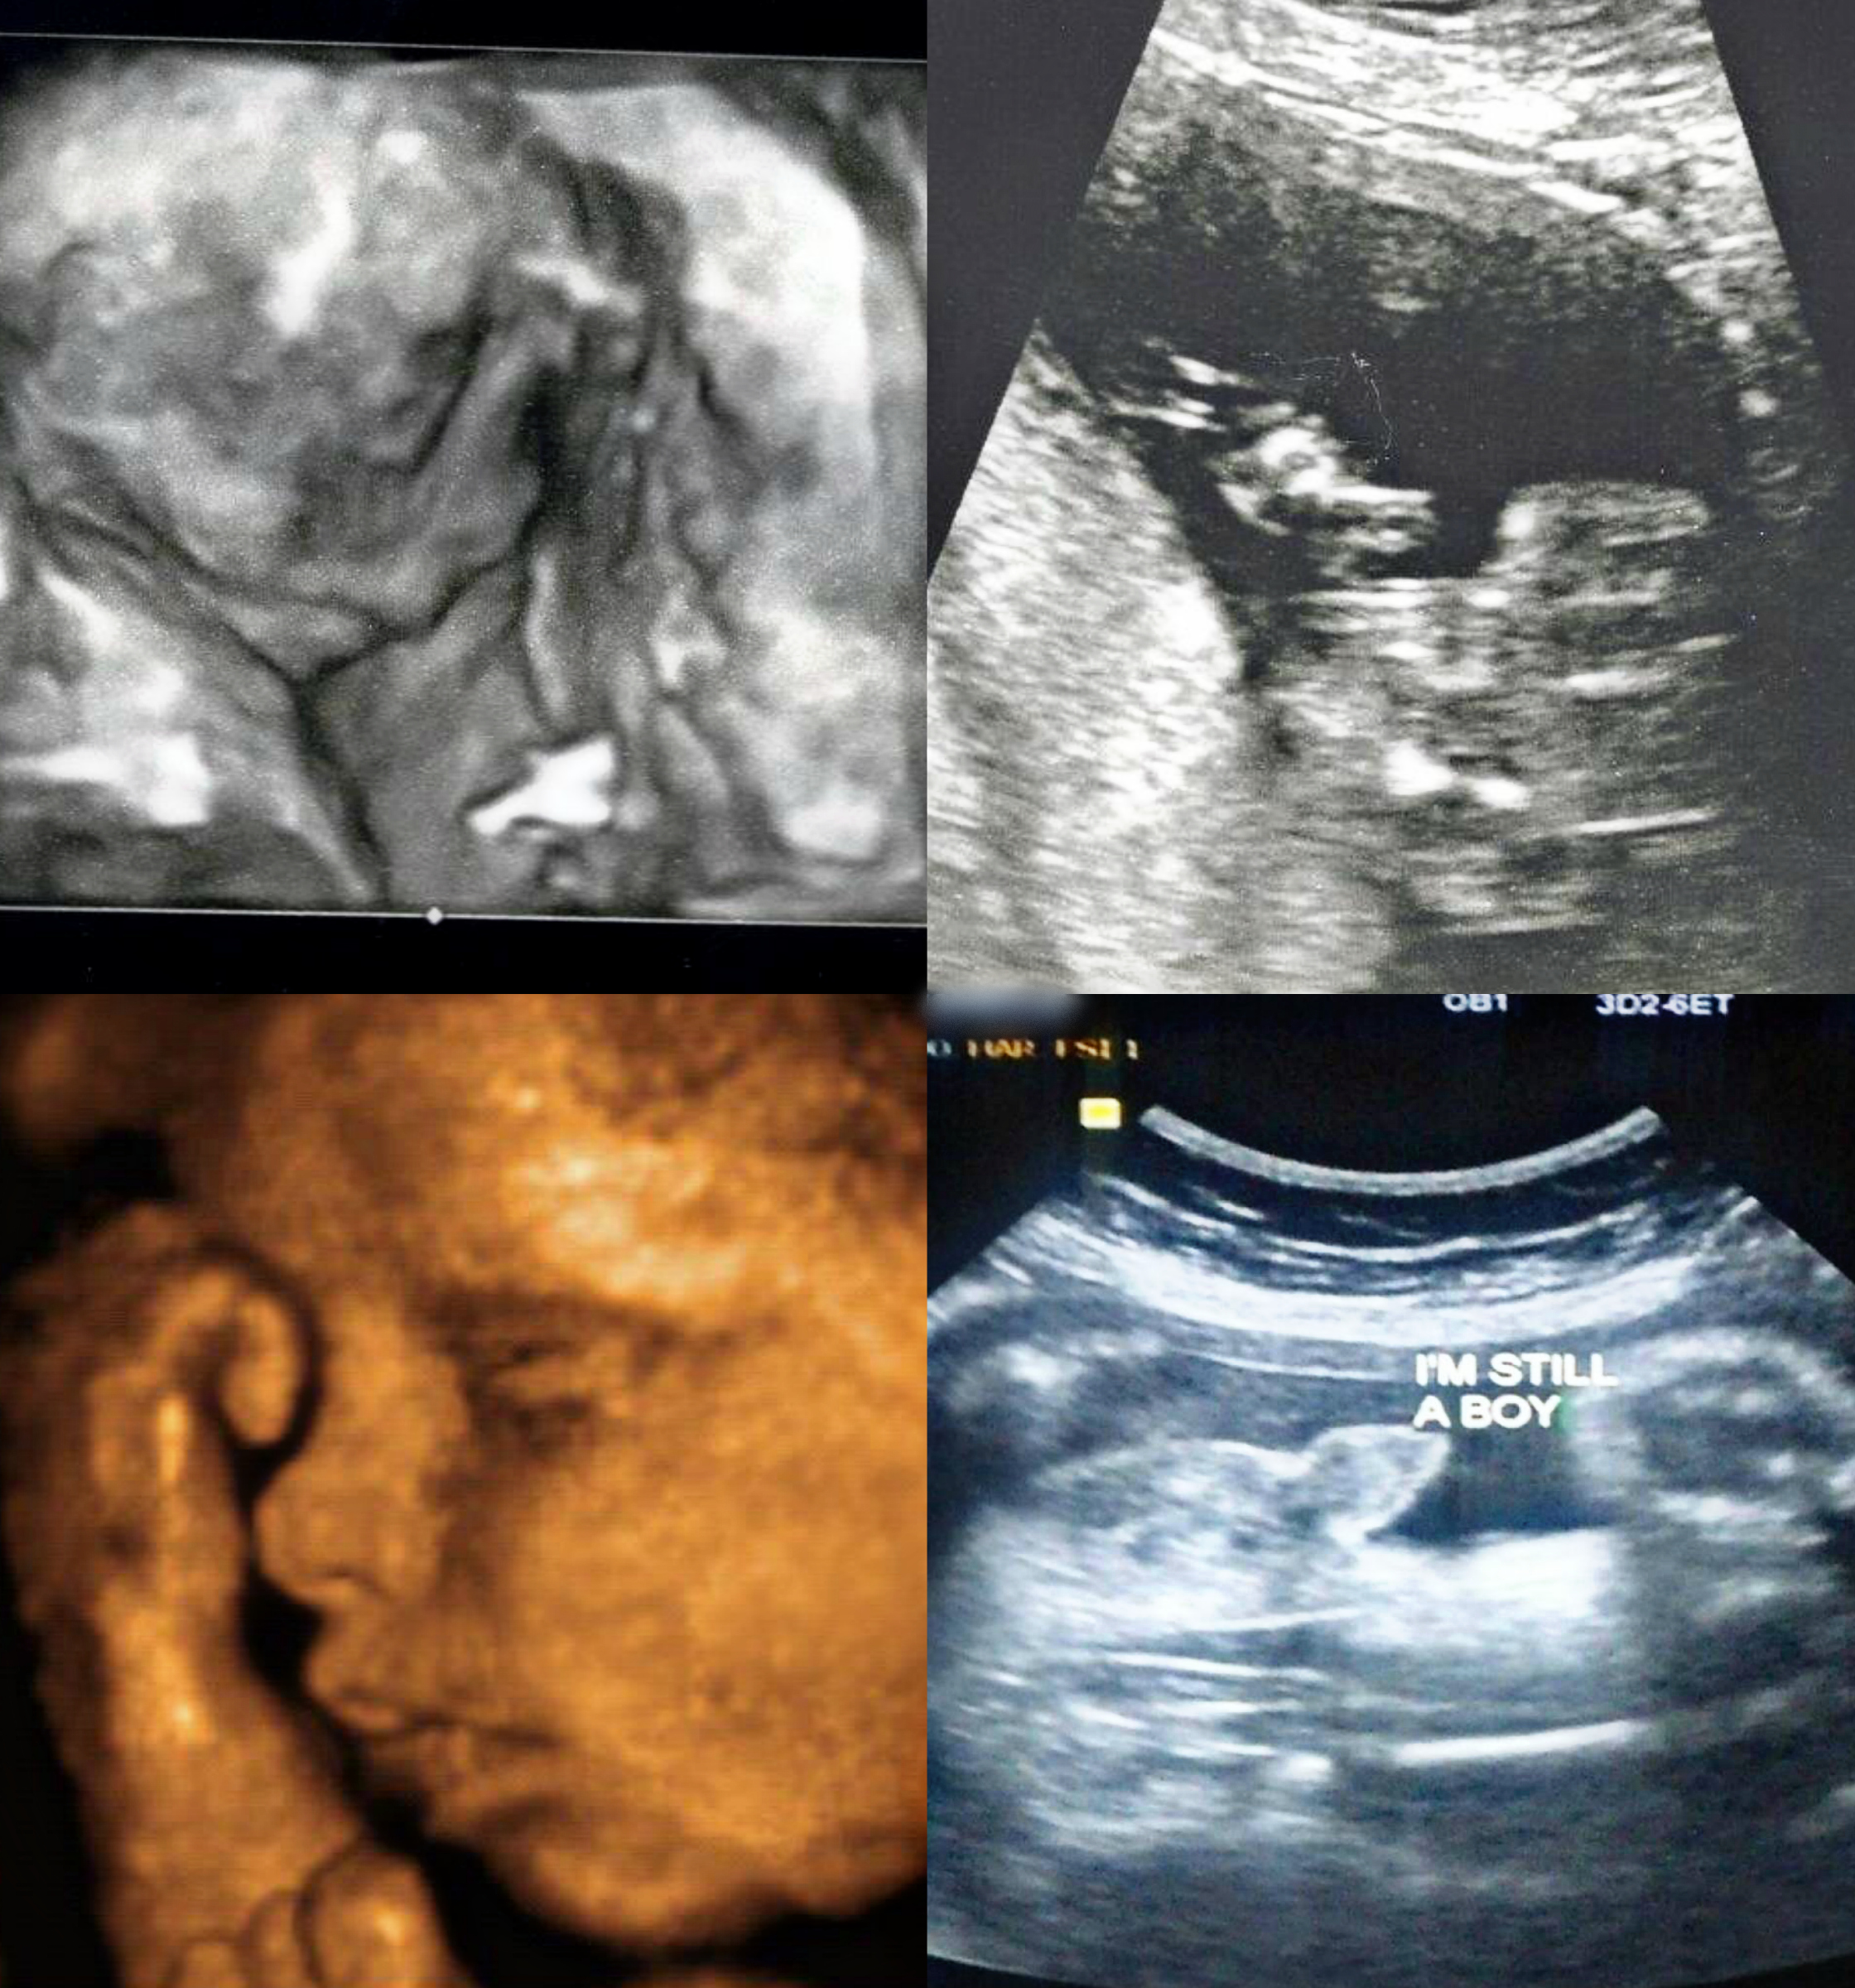

Anyways this is the scan potty shoots! The first one she said was boy

Attachment 20274Attachment 20275Attachment 20276